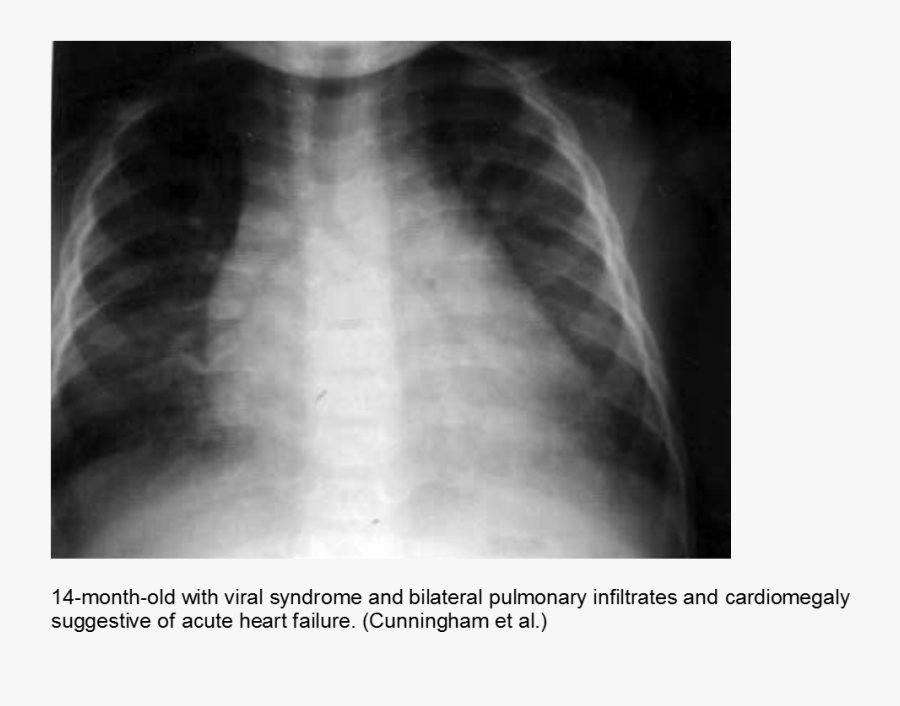

From ylamsang.net

Save the life of a case of fulminant myocarditis in a 4monthold infant Chest X Ray Myocarditis Myocarditis, which affects people of all ages (symptom onset typically between 20 and 50 years of age), has a wide. Will often be normal in myocarditis, but it may show. Myocarditis is a condition where the heart muscle becomes inflamed. Myocarditis is a disease marked by the inflammation of heart muscle. Specifically, this is an infection of the myocardium, which. Chest X Ray Myocarditis.